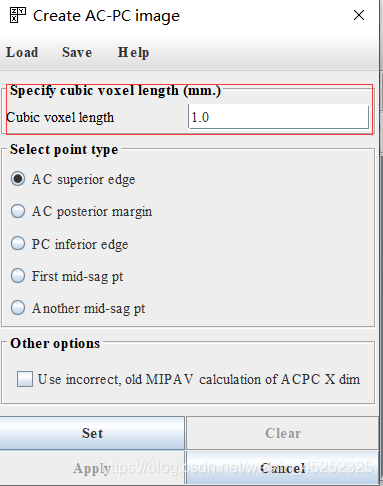

(1) 设置精度,一般默认1.0

对于每个点,在三平面视图中的适当位置设置十字准线

(2) 第一个目标标记AC上中部和后中部

③ 设置AC上边缘(superior edge)

⑥ 设置AC后缘(posterior margin)

找到AC superior edge,点击set

找到AC posterior edge,点击set

(5) 第三个目标是标记两个中矢状点(胼胝体上方)(这一步在文中没有详细描述,所以有点模糊,参考另一篇参考)

First midsagittal point和Another midsagittal point,要求二者之间距离在20mm以上,一般就选择在和AC,PC同一矢状面上(在实践中,SG1和SG2的好候选者通常远离AC和PC,彼此之间也远离)

(6)保存变换信息:最后点击Apply,会显示ACPC结果(和原图),可以点击save保存变换信息